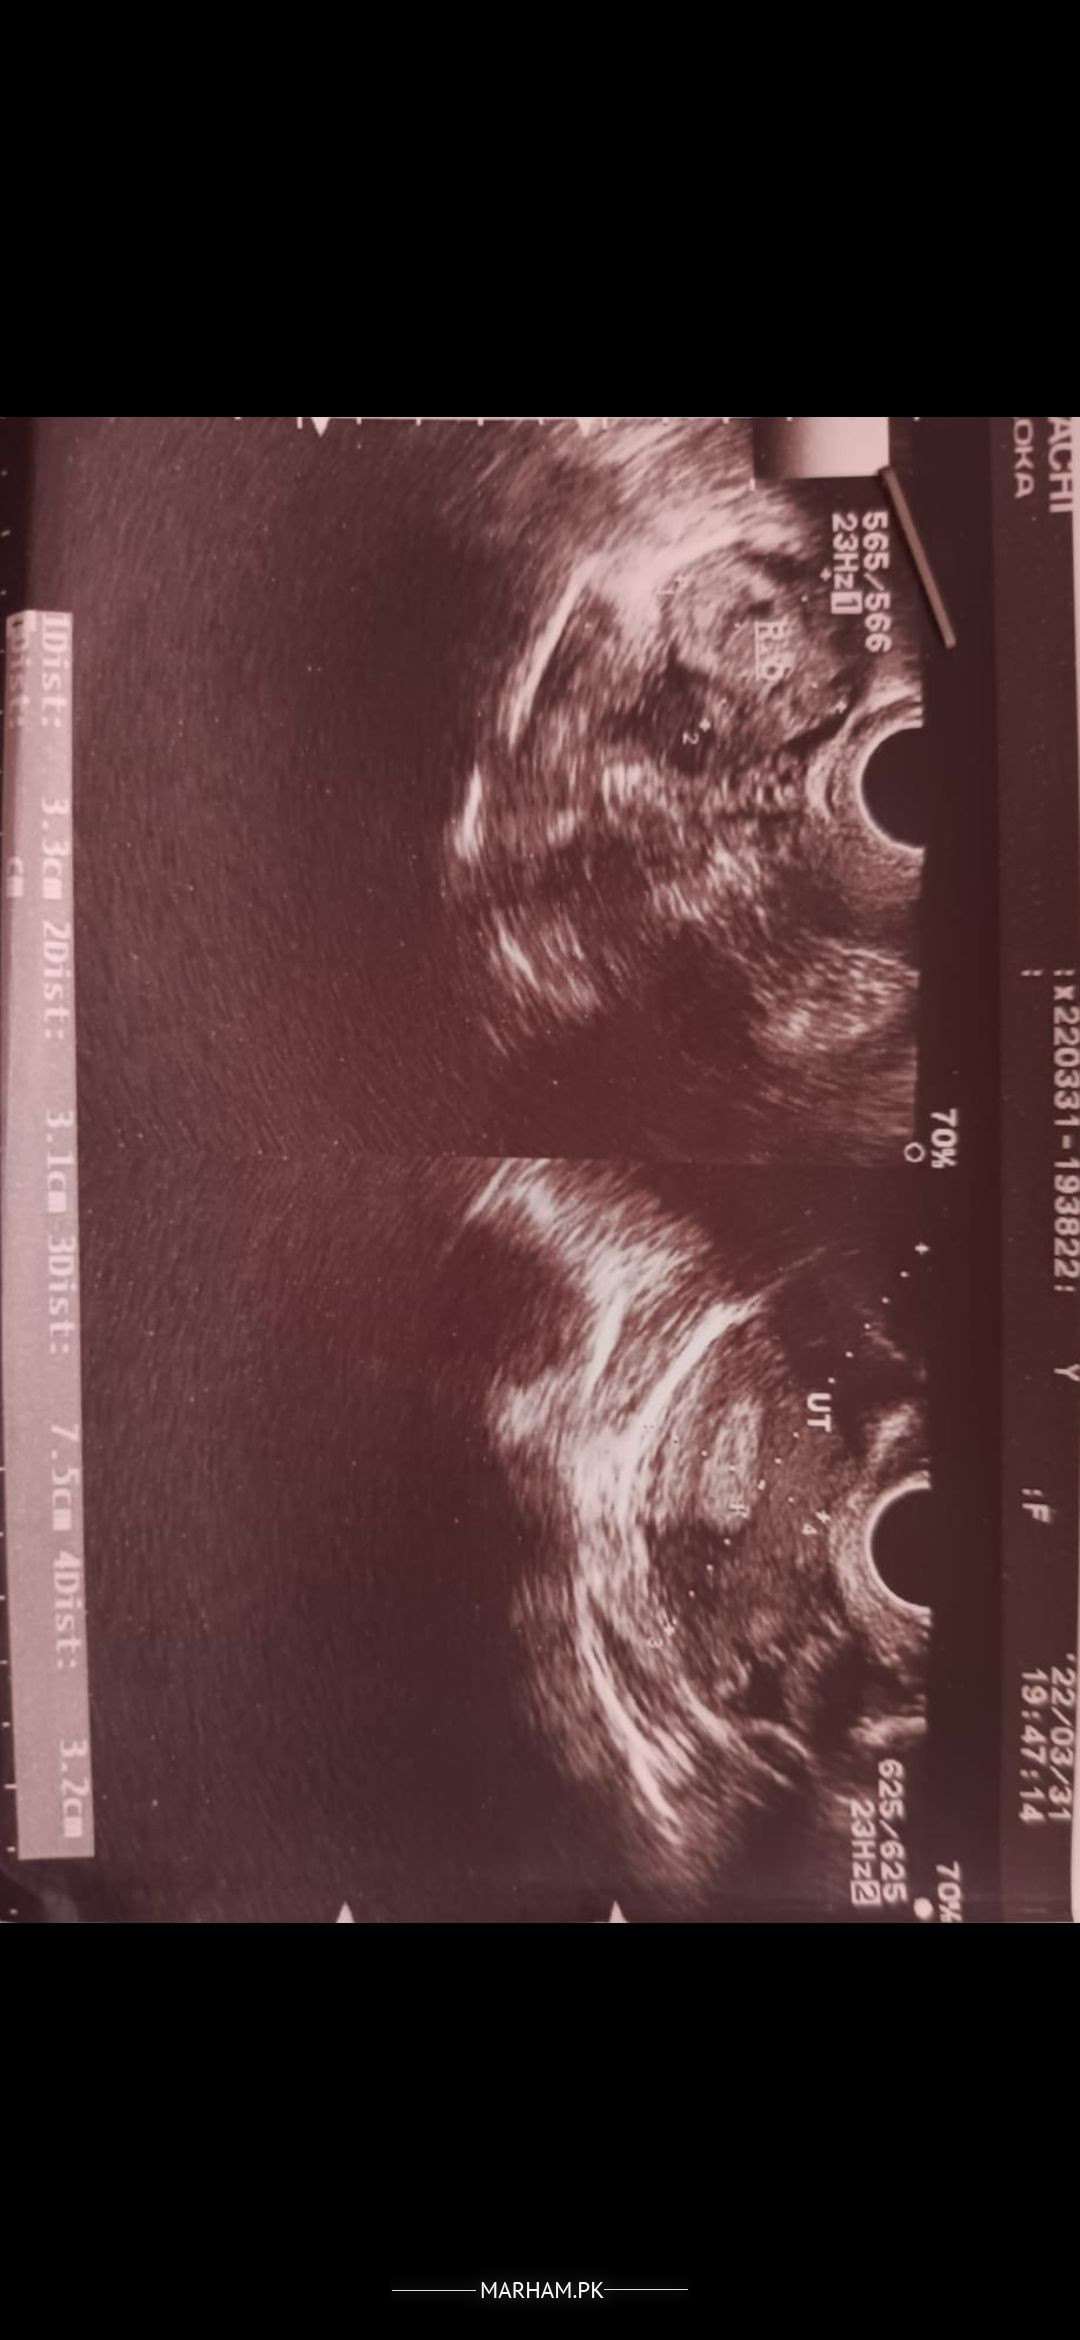

Can any doctor please describe the intensity of cysts some doctor told me that I have raptured ovaries etc and really scared. I just got married and it's too scary for me

It's only report available at the moment

You have polycystic ovaries which is a condition of ovary which does not make good eggs and delay fertility. There is no rupture.

you've PCOs dear which causes irregular periods and delay pregnancy.